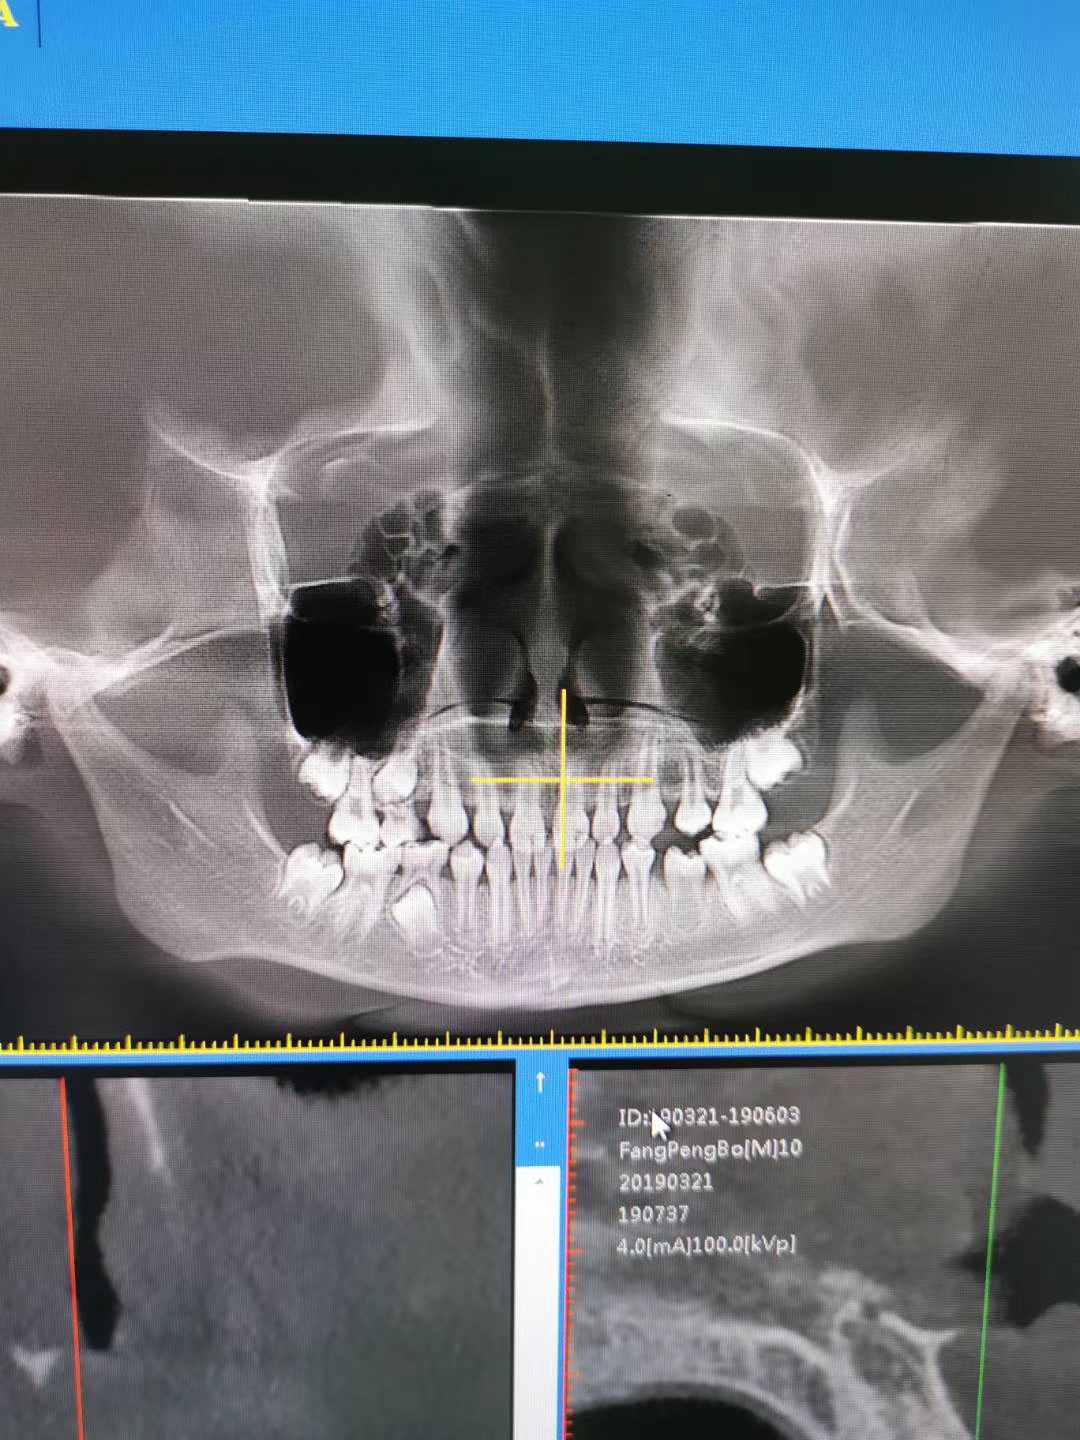

小朋友是替牙期,骨性地包天,做了一年多的前牵引,现在达到目标了。

图片发自160医生App